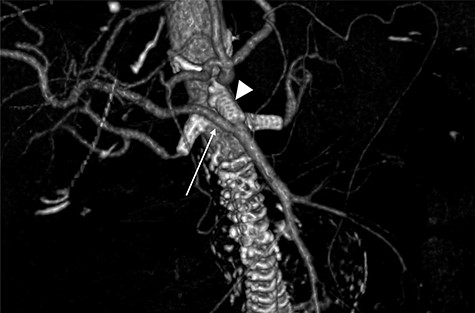

Although this was a planned elective FEVAR, several complications requiring two laparotomies, multi-organ dysfunction as well as patient’s multiple comorbidities contributed to prolonged intensive care unit (ICU) stay and delayed discharge. However, a multidisciplinary approach involving relevant specialties had allowed him to make a good recovery for rehabilitation and discharge home. Surveillance CT aorta at 1 month and 6 months post FEVAR showed satisfactory FEVAR appearance with no endoleak (Fig. 5).

Follow-up CTA showing all visceral stents patent and RRHA (arrow) from SMA (arrowhead).